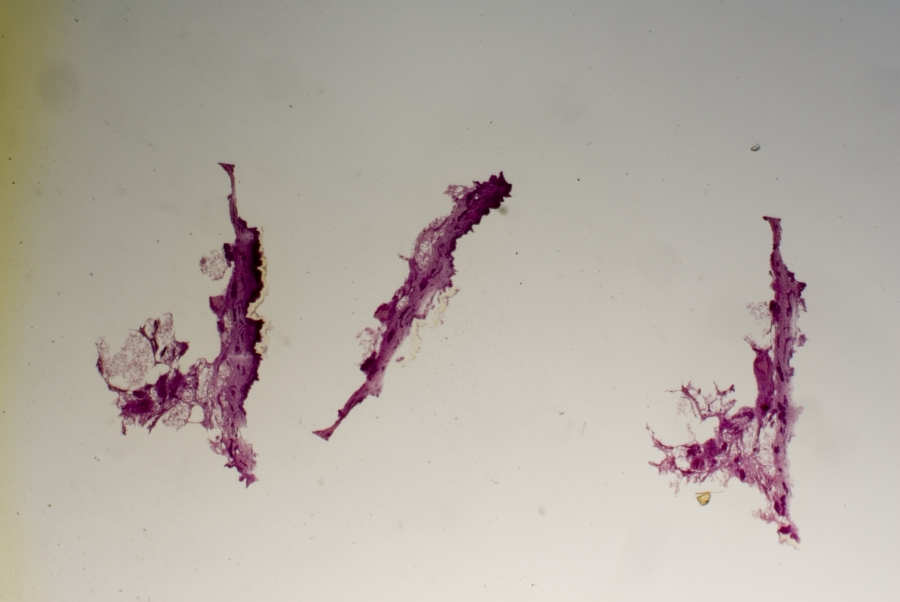

Image Filename: 35163_3666-1

35163_3666-1

container invno 35163

specimen id 3666